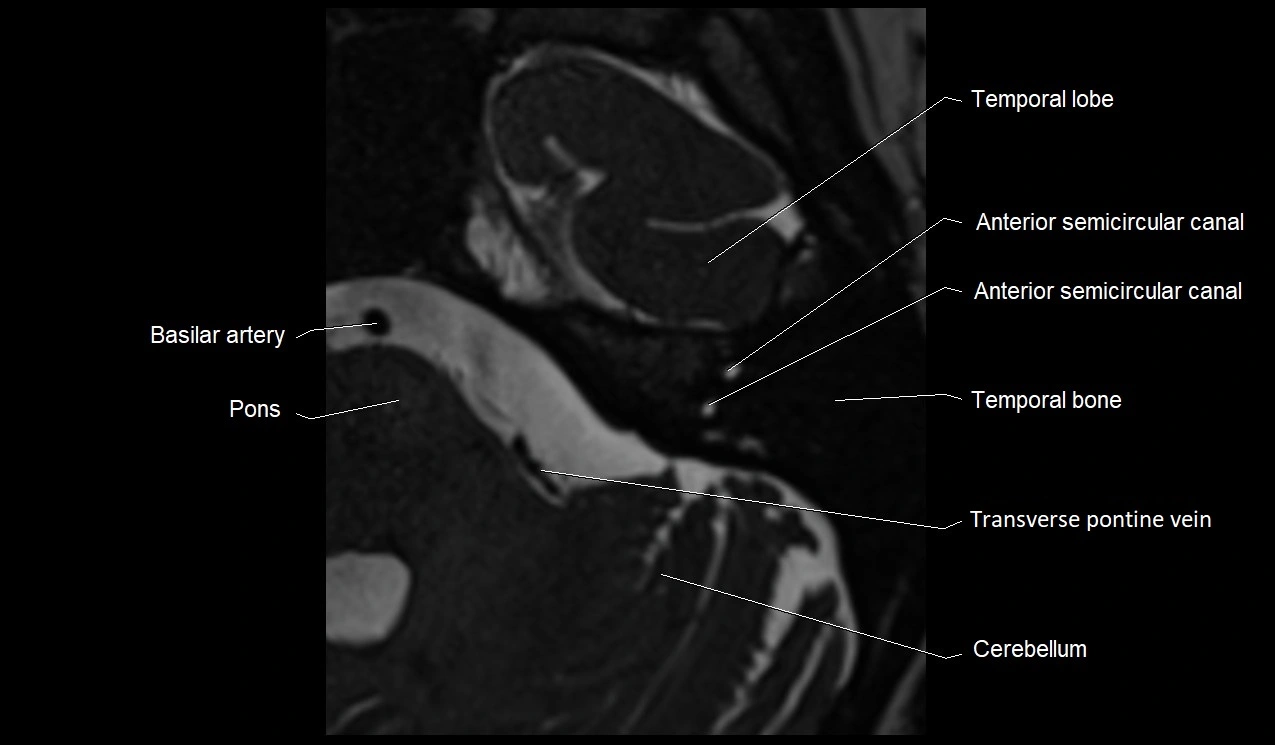

MRI images

image